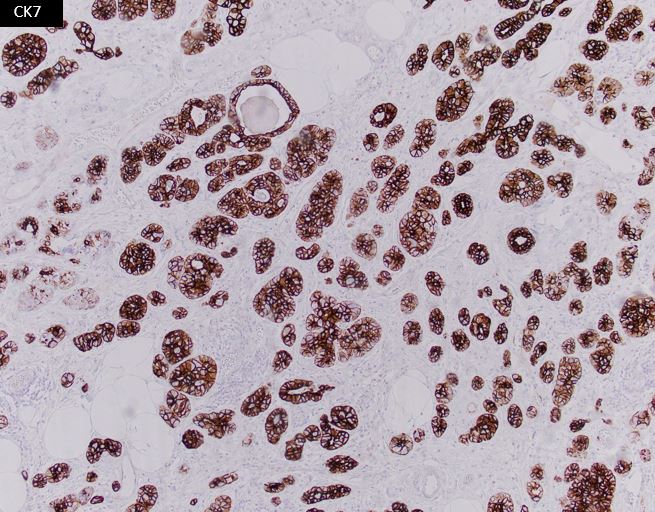

A 75-year-old woman presents with a 3 cm breast mass, undergoes lumpectomy. The neoplastic cells are positive for CK7, S100, and lysozyme.

ACC is characterized by serous acinar differentiation with zymogen-type cytoplasmic granules. The immunohistochemical profile of breast Acinic cell carcinoma shares many features with Acinic cell carcinoma of the salivary glands, with frequent expression of GCDFP-15, S-100, and a-1-Antichymotrypsin, as well as PAS-D positivity.